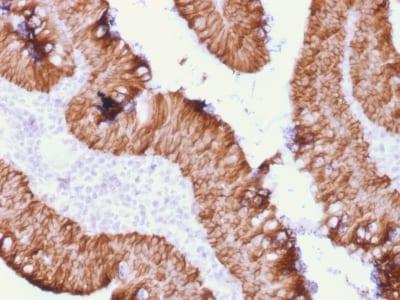

EGP40 is a 40-43 kDa transmembrane epithelial glycoprotein, also identified as epithelial specific antigen (ESA), or epithelial cellular adhesion molecule (Ep-CAM). It is expressed on baso-lateral cell surface in most simple epithelia and a vast majority of carcinomas. This antibody has been used to distinguish adenocarcinoma from pleural mesothelioma and hepatocellular carcinoma. This antibody is also useful in distinguishing serous carcinomas of the ovary from mesothelioma.Primary antibodies are available purified, or with a selection of fluorescent CF® Dyes and other labels. CF® Dyes offer exceptional brightness and photostability. Note: Conjugates of blue fluorescent dyes like CF®405S and CF®405M are not recommended for detecting low abundance targets, because blue dyes have lower fluorescence and can give higher non-specific background than other dye colors.

HT29 cells or Ovarian carcinoma

Plasma membrane

Cell tissue expression

Epithelial cells

Adenocarcinoma

Higher concentration may be required for direct detection using primary antibody conjugates than for indirect detection with secondary antibody|Immunohistology (formalin): 0.5-1 ug/mL for 30 minutes at RT|Staining of formalin-fixed tissues requires boiling tissue sections in 10 mM citrate buffer, pH 6.0, for 10-20 minutes followed by cooling at RT for 20 minutes|Western blotting 0.5-1 ug/mL|Optimal dilution for a specific application should be determined by user